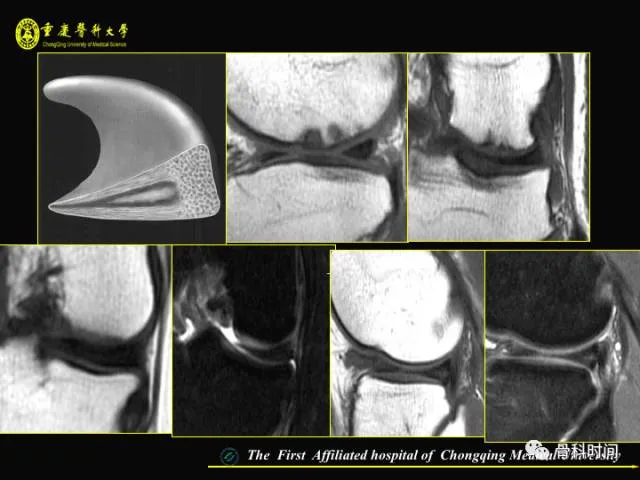

你知道半月板损伤的 MRI 是如何分级的吗?半月板撕裂的 MRI 表现又是怎么样的?

今天给大家分享一份精美 PPT,全方位详述膝关节半月板 MRI 的要点,一起来学习一下: